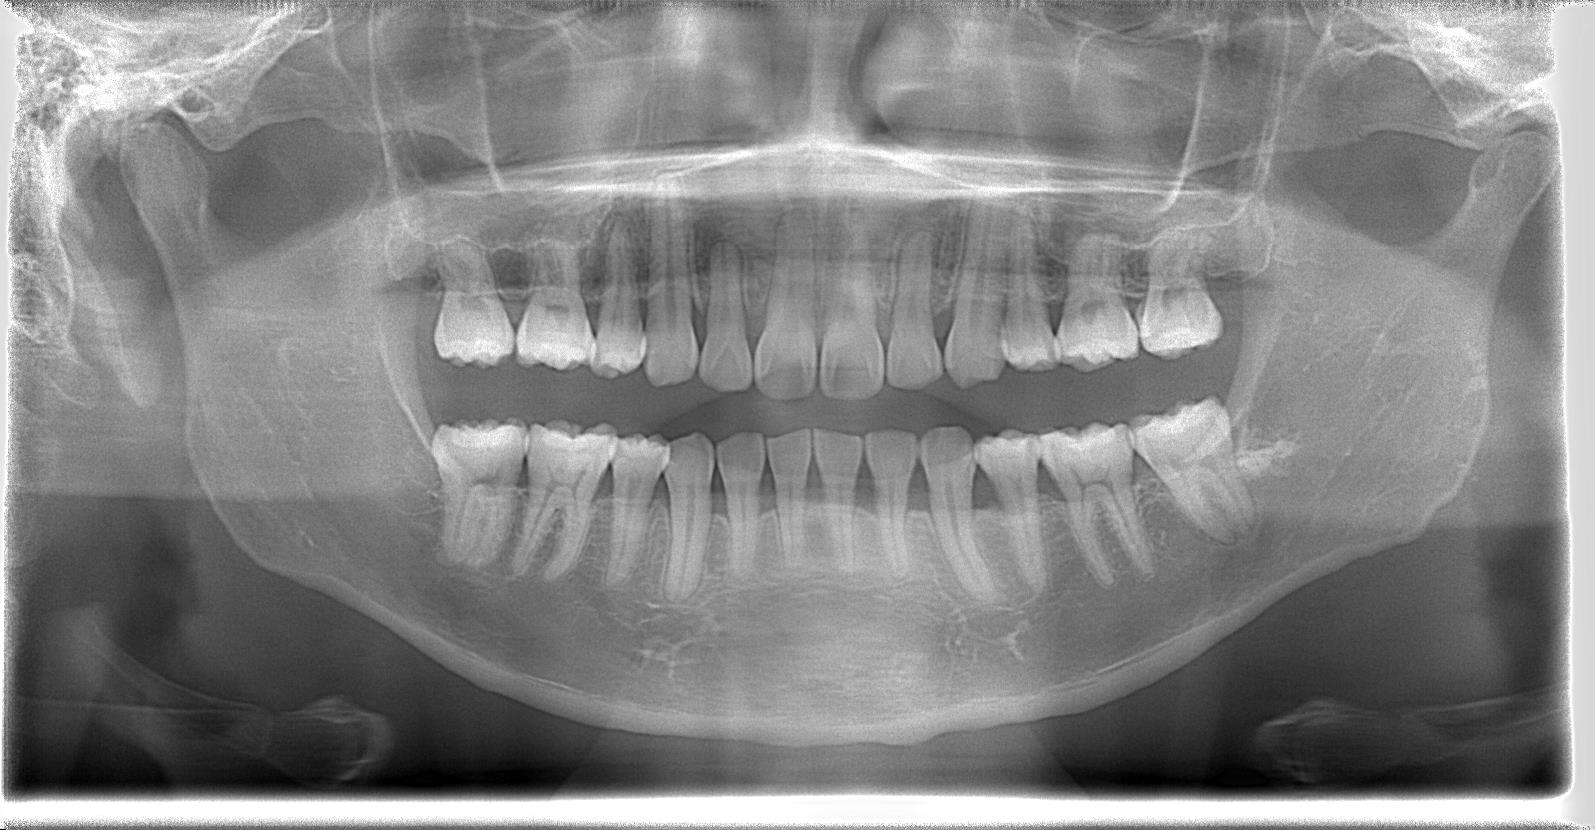

[術前パノラマレントゲン写真]

[治療後のパノラマレントゲン写真]

第3大臼歯を抜歯して矯正配列している症例です。